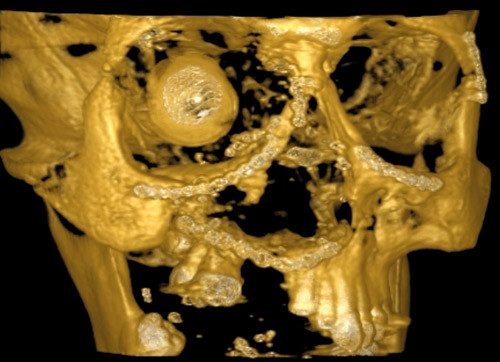

Fig. 1 shows a DVT image of a patient with bullet wounds after the implantation of a large amount of osteosynthetic material. This method resulted in an image without artefacts, whereas traditional CT was of limited use because of metal artefacts and unsatisfactory 3D modelling (Fig. 2).

Figure 1  CBCT 3D midface reconstruction